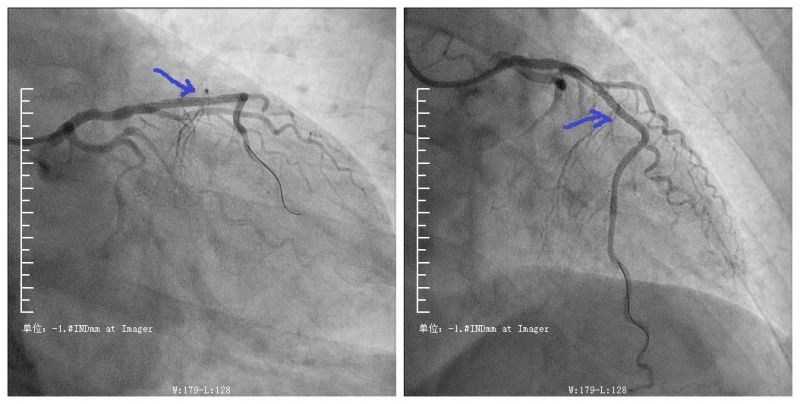

上图所示为开通后的血管

今年63岁的芝罘区居民老李,平日里自觉身体良好。前两天的一个下午他突然感到胸口闷痛,时好时坏,当时他也没当回事。第二天再次出现胸闷、胸痛等症状,疼痛的程度比昨日明显加重,他随即赶往烟台山医院南院区就诊。在这里,老李接受了心电图检查,医生考虑诊断为“冠心病 急性心肌梗死”。医生通过急诊手术为老李开通闭塞的心血管,老李转危为安,此前胸闷、胸痛的症状也随之消失。

烟台山医院是第一批通过中国胸痛中心认证的医院,同时也通过了美国胸痛中心的认证,长期致力于急性心肌梗死的急诊急救工作。烟台山医院南院内二科为心脑血管病科,在急性心肌梗死药物溶栓治疗及急诊微创手术开通冠状动脉等方面,具有丰富的救治经验。烟台山医院南院内二科专家提醒大家,疫情期间,更需关注心脏健康,如出现胸闷、胸痛等心脏不适症状一定要及时就医。